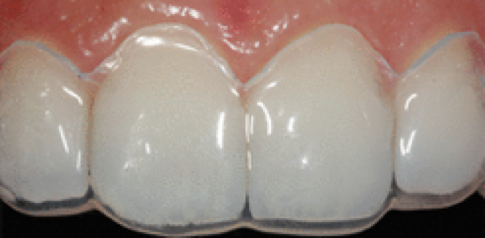

了解與牙周病的發展,也可幫助民眾做簡單的自我檢查,以便早期發現、早期治療。健康的牙齦組織為但淡粉紅色,牙齦結實。一旦牙菌斑累積,初期會引發牙齦炎,此時牙齦外觀紅腫,刷牙時牙齦會出血。當牙齦發炎沒有即時控制治療,牙齦炎將發展至牙周病,病患會發現牙齦明顯退縮、牙縫越來越大、牙齒開始對冷熱酸痛敏感、口臭、牙齒搖動,咀嚼時不如以往紮實有力,甚至會有疼痛感,嚴重者口內會出現化膿現象。